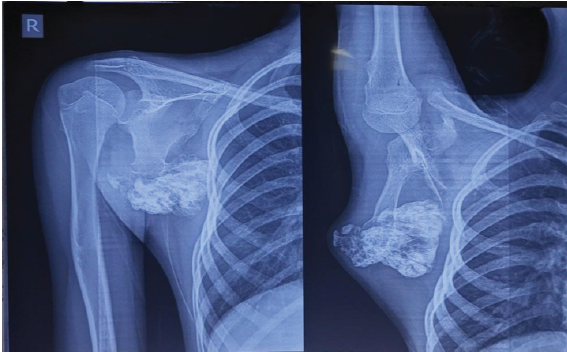

Plain radiographs and computed tomography (CT) of the right scapula revealed a large, pedunculated exostosis arising from the dorsal aspect of the scapula (Fig. 3). Multiple pedunculated bony lesions from the bilateral distal femur and proximal tibia were noted. Surgical excision of the scapular mass was elected, while the knee lesions were left under observation since there were no clinical complaints.

Figure 3: Preoperative shoulder radiograph (antero-posterior and scapular Y views) showing a large, well-circumscribed, pedunculated bony mass arising from the inferior angle of the right scapula.